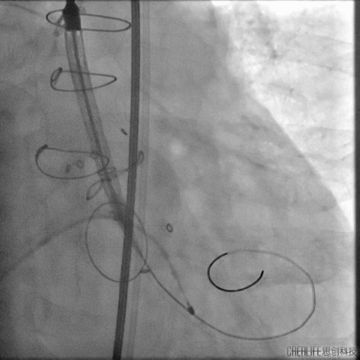

主动脉瓣架释放

复查造影

跨瓣压差下降为20左右,超声复查微量瓣周漏,瓣膜植入位置良好,遂闭合入路送回病房,一周后康复出院。